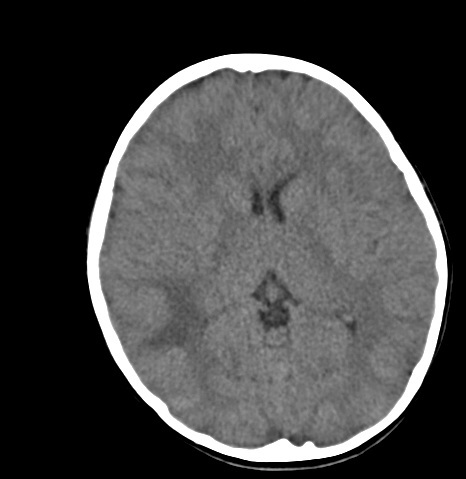

Pineal Gland Tectal Plate

Gross anatomy the pineal gland typically measures around 7 x 6 x 3 mm in size and is situated in a gr. It is unpaired and situated in the midline.

Their importance is mainly in the fact that they cannot be distinguished from cystic tumors especially when large or when atypical features are present.

Pineal gland tectal plate. Pineal cysts are common usually asymptomatic and typically found incidentally. But we now know that pineal gland function is to control the sleep wake cycle circadian rhythm by. The pineal gland is a small pine cone shaped structure considered to be part of the epithalamus.